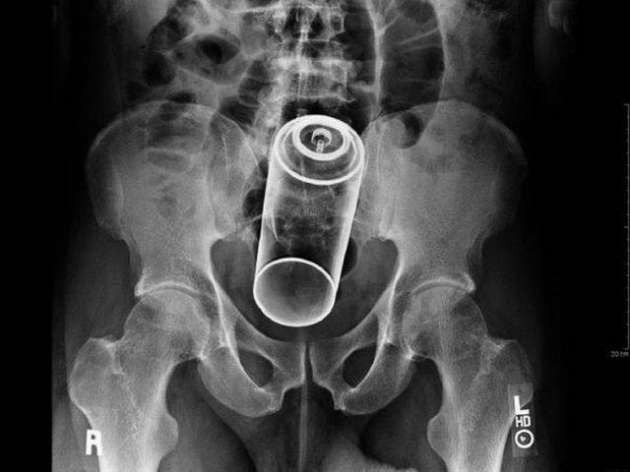

İÇİNDEKİ ŞEYE RÖNTGEN UZMANLARI ŞOK OLDU!

23 Ocak 2016 Cumartesi 17:38RÖNTGEN UZMANLARI ŞOK OLDU!

,Dünyada çekilen bu röntgenler hem röntgen uzmanlarını hemde görenleri şok ediyor...